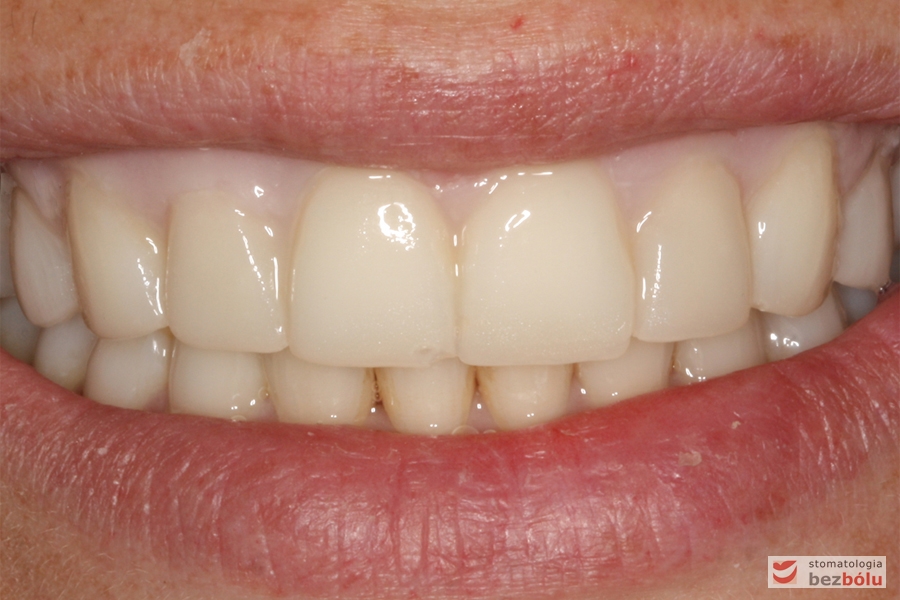

Analiza uśmiechu po zacementowaniu pracy ostatecznej - en face

Analiza uśmiechu po zacementowaniu pracy ostatecznej – en face

Pozytywna przemiana uśmiechu - obraz kliniczny po terapii stomatologicznej

Pozytywna przemiana uśmiechu – obraz kliniczny po terapii stomatologicznej